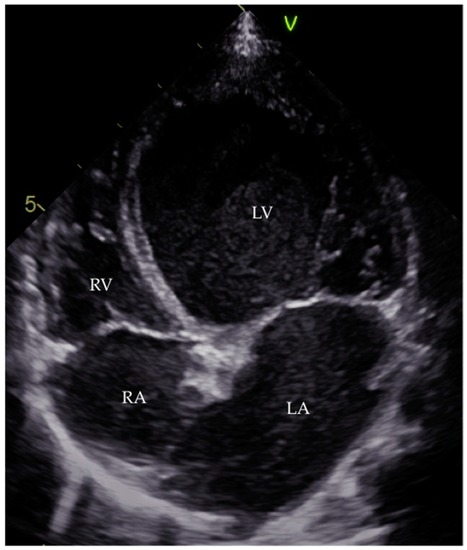

- Goitein, O.; Matetzky, S.; Beinart, R.; di Segni, E.; Hod, H.; Bentancur, A.; Konen, E. Acute myocarditis: Noninvasive evaluation with cardiac mri and transthoracic echocardiography. AJR Am. J. Roentgenol. 2009, 192, 254–258. [Google Scholar] [CrossRef] [PubMed]

- Pinamonti, B.; Alberti, E.; Cigalotto, A.; Dreas, L.; Salvi, A.; Silvestri, F.; Camerini, F. Echocardiographic findings in myocarditis. Am. J. Cardiol. 1988, 62, 285–291. [Google Scholar] [CrossRef]